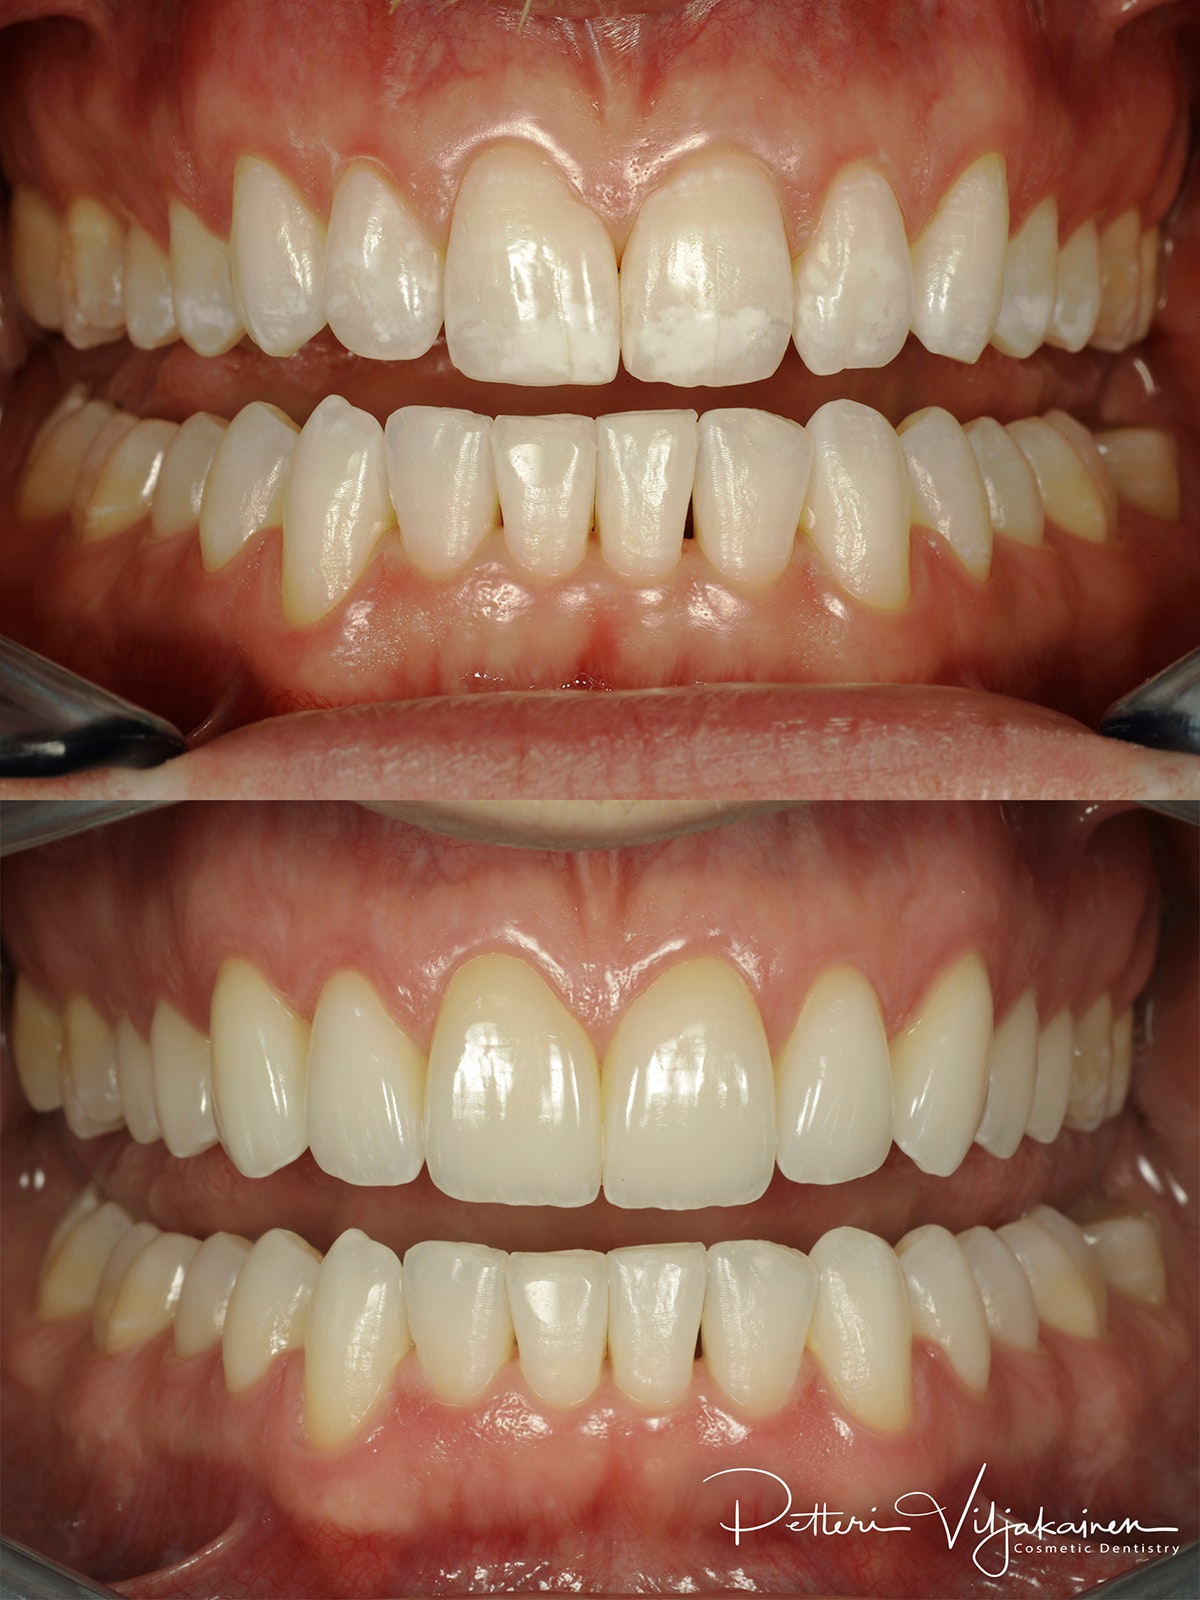

Keraamiset hammaslaminaatit kymmenessä ylähampaassa

Sama tilanne hymyillessä.

4. Keraamiset hammaslaminaatit kymmenessä ylähampaassa